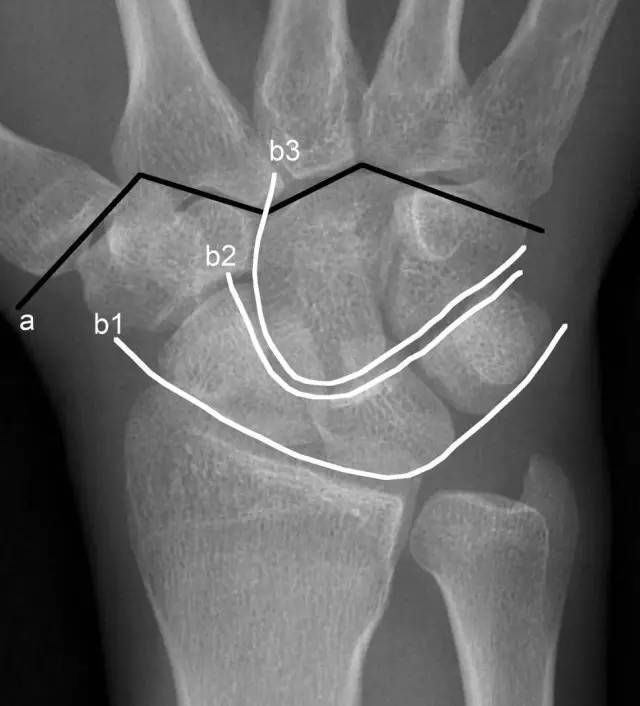

腕骨弧线(gilula线)3,如何判断是否有月骨脱位有人提出这样一种观点

图片尺寸640x706